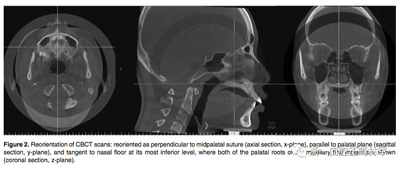

在治療前(T1)和擴弓后3個月(T2)拍攝CBCT,獲得的數(shù)據(jù)由In Vivo Dental(Anatomage,San Jose,Calif)分析。為了在T1和T2階段設置相同的參考平面,CBCT圖像沿著腭中縫(x平面)定向,平行于腭平面(y平面)并且與鼻底(z平面)相切(Figure 2)。在腭中縫處評估橫向骨骼擴張,并在三個不同的平面進行線性測量:鼻底,硬腭和硬腭以下5mm。在根尖和牙冠水平測量橫向牙齒擴張(Figure 3)。評估兩側的牙槽傾斜度,牙長軸,牙齒垂直高度和骨開裂等情況(Figure 4,5)。所有測量均在每個上頜前磨牙和磨牙區(qū)域進行。